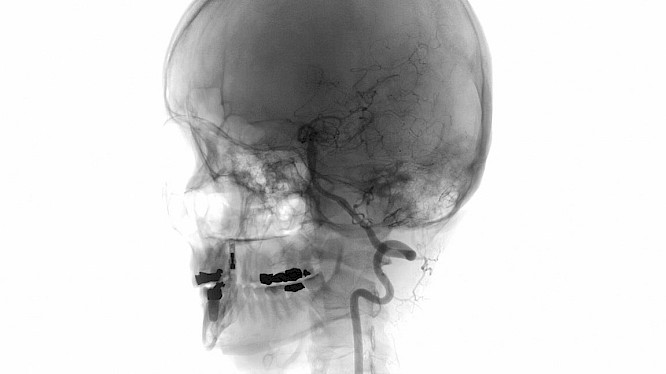

The diagnosis: an aneurysm in the brain. Then follow two nightmarish months during which we accompany the filmmaker. An essayistic audio-visual collage, in which Sobo Swobodnik shows us what it means to live with a potentially fatal condition.